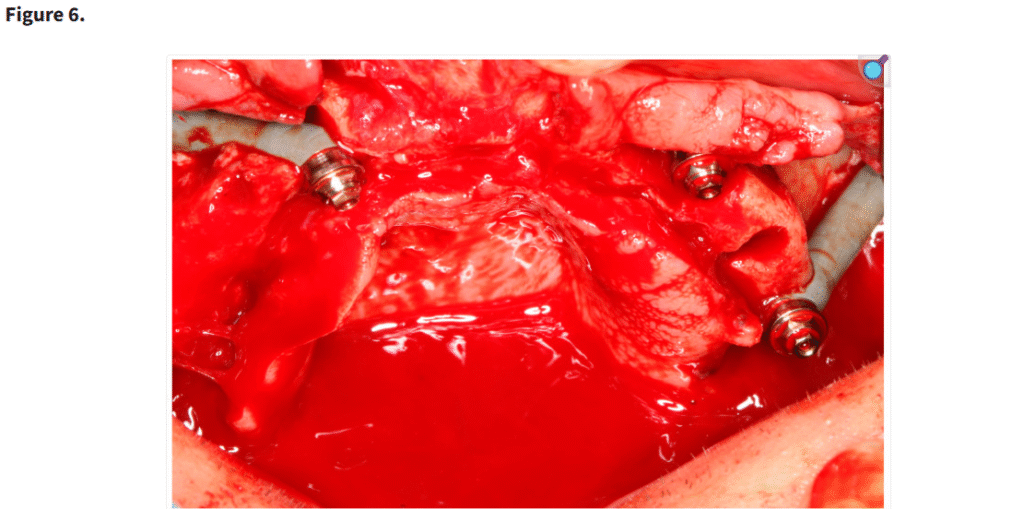

ザイゴマインプラントは、「サイナススロットアプローチ」とエクストラサイナス技法を組み合わせて使用し、最適なインプラント固定と補綴的支持を得た(Figure 6)

エクストラマキシラリー法によるザイゴマインプラント埋入

正確なインプラント埋入を可能にするため、ダイヤモンドバーを用いて側方上顎洞ウィンドウを作製した。この操作により、上顎洞天蓋の直視下での確認が可能となり、インプラントの安全かつ正確な位置決めが容易になった。上顎洞粘膜は穿孔や損傷を避けるために慎重に挙上され、インプラント挿入のための明確な経路が確保された。

頬骨へのドリリングは、回転数600 rpmに制御されたインプラント用ハンドピースを用いて行われた。その後、Nobel Biocare社製のザイゴマインプラント(TiUnite表面、45度アングル、直径4.3 mm)が埋入された。インプラントの長さは患者ごとの解剖学的条件に基づき、30 mmから52.5 mmの範囲で選択された。